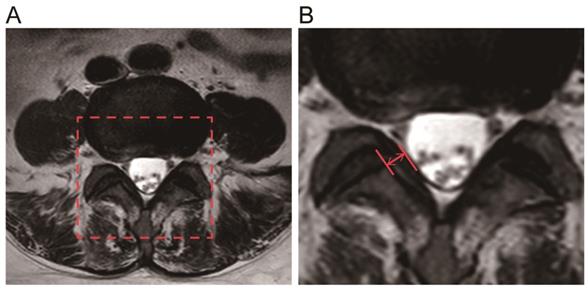

Measurement of LF thickness

Preoperative magnetic resonance images(MRI, Philips, Amsterdam, Netherlands) were collected from all 50 patients, two parallel lines were drawn along the direction of the ligamentum flavum on axial T2-weighted images through the facet joint, and the maximum distance between the dural side and the dorsal side was chosen, using PACS(Picture Archiving and Communication Systems) workstations (an image analyzing system, Nanfang Hospital of Southern Medical University, Guangzhou, China) to measure the maximum thickness of the LF. Each ligament flavum was measured three times, and the average value was taken as the final LF thickness [26, 27].

The LF thickness of the two patient groups was measured via MRI(Fig. 1), and the results showed that the mean thickness of the LF in the LSCS group(5.81±0.51mm) was significantly higher than that in the Non-LSCS group(2.72±0.45mm) (Table 1). Histological examination of HE staining & Masson trichrome staining (Fig. 2A) showed that compared with the Non-LSCS group, the LSCS group had fewer elastic fibers and more disordered and heterogeneous collagen fibers. This indicated that the LF fibrosis degree was higher in the LSCS group.

Fig 1

Measurement of the LF thickness by MRI. A The red frame was selected as the target analysis area. B The red arrow indicates the thickness of the ligamentum flavum at the facet joint level.